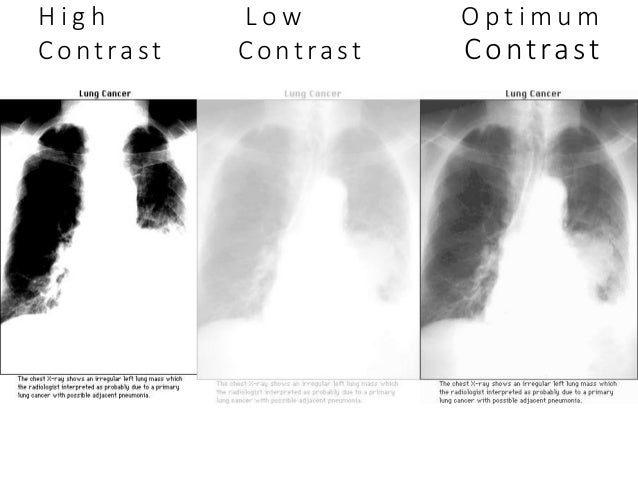

Kvp And Contrast Radiology Humor Radiology Radiology Imaging

In radiology the difference between the image densities of two areas is the contrast between them. A primary beam with greater kv results in an overall rise in penetration through all tissues decrease in attenuation differences therefore resulting in a lower contrast radiograph. Because bones block the x rays easily they show up clearly. Generating x rays using a low kilovoltage will generally result in a radiograph with high contrast.